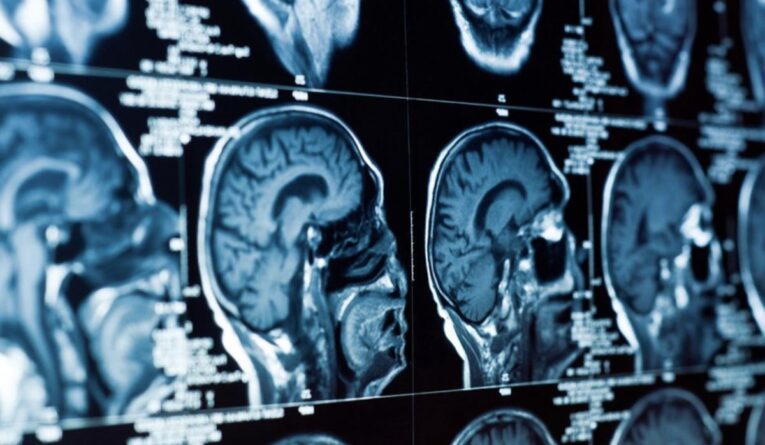

- Магнитно-резонансная томография (МРТ): используется при подозрении на опухоли или сложных воспалительных процессах.